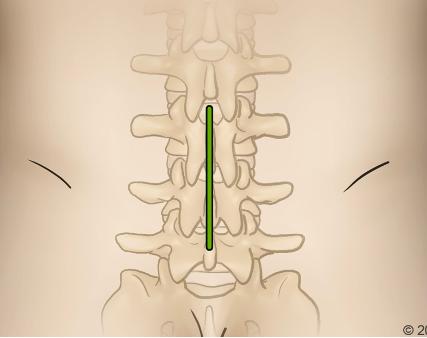

MarkingandIncision:Fluroscopy&Palpationof Sacrum,IliacCrests(Lumbar)orvertebra prominens/sternalnotch(Cervical);3to4-cm longitudinalincisiontoexposeinterspinousspace

Dissection:Electrocauterydissectionof subcutaneoustissue,revealslumbarfascia Blunt dissectionuntilfacetsarereached

3. Facetectomy/Laminectomy:Medialaspectofthe inferiorfacetofthesuperiorvertebramaybe resectedalongwithpartofthelaminatoallowfor exposure RemovalofLigamentumFlavumafterthis toexposehernia(LumbarRegion).